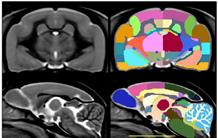

Des chercheurs de l'Institut François-Jacob ont créé un atlas anatomique numérique du cerveau du plus petit primate existant sur terre, le microcèbe murin (Microcebus murinus). Ce lémurien, doté d’un cerveau minuscule (2 grammes), est parfois considéré comme peu évolué car éloigné phylogénétiquement de l’homme. Ces chercheurs ont comparé son atlas cérébral avec celui d'autres espèces de primates (marmoset, macaque, homme). Ils ont montré que le ratio entre le volume du néocortex et l'ensemble du cerveau est constant chez tous les primates (proche de 56%). En d'autres termes, même si l'homme ou les singes ont un cerveau plus gros que celui des microcèbes, la part du néocortex sur l'ensemble du cerveau reste la même. Cette découverte remet en cause le dogme suggérant que l'évolution des primates est liée à une augmentation de la taille relative de leur néocortex. Ce dogme était basé sur des études post-mortem de cerveaux d’animaux réalisées avec des techniques tellement complexes qu'elles n'ont été mises en œuvre qu'une seule fois dans les années 80. Les scientifiques ont travaillé avec des données d'imagerie par RMN (résonance magnétique nucléaire) qui sont, elles, complétement reproductibles et utilisables par toute la communauté scientifique.

En revanche, l'étude montre que le ratio entre le volume de substance blanche (zone cérébrale contenant les fibres qui permettent à différentes régions du cerveau de communiquer entre elles) et l'ensemble du cerveau varie considérablement selon les types de primates. Ce ratio semble corrélé au niveau de développement cérébral et cognitif de l’espèce. En effet, il est faible chez le microcèbe, intermédiaire chez le macaque et maximal chez l’homme. Ces résultats mettent donc en évidence l'importance variable des réseaux de substance blanche chez les primates. Ces nouvelles données sont importantes pour mieux comprendre comment les cerveaux ont évolué et les règles qui expliquent leurs organisations. Ils montrent aussi l'importance des techniques d'imagerie pour explorer le cerveau.